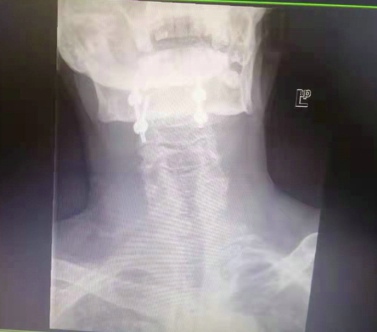

术后X光片,显示寰枢椎脱位已获得解剖复位,椎弓根钉位置良好,寰椎后弓切已除,延髓受压解除